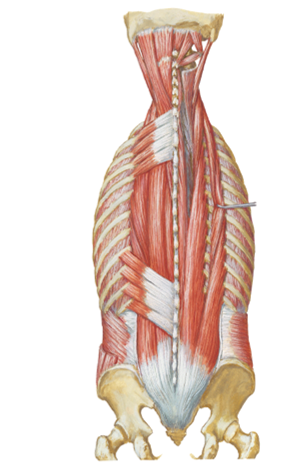

what 3 things to assess during a PE with patterns of ventilation?

what 2 things should we look for in inspiration?

Physical exam ...assess rate, symmetry, quality of movement, etc…

Inspiration ...increase in AP and lateral diameter due to “bucket

handle” motion of ribs

increase superior to inferior length

look at pictures to help visualize

inspiration while at rest and not exercising involves what 2 muscles?

with exercise what 3 muscles can help out with inspiration?

diaphragm and external intercostals

accessory muscles like the SCM and scalenes can help...pecs can also help

expiration while at rest and not exercising involves what?

with exercise what muscles get recruited to help with expiration?

- rest...elastic recoil of the lungs

- exercise...recruit the internal intercostals + abdominal muscles like (rectus abdominis, int/ext oblique)

what is one abnormal movement pattern of ventilation? who typically displays this?

name another abnormal ventilation quality? when do you typically see this with?

“Shrug” shoulders...Patients with COPD and other pulmonary disease may display this type of breathing pattern

Asymmetry... see this with trauma/pathology to one lung

- Ex: pneumothorax, etc…

Identify/describe actions of the following muscles

- Levator costarum (lc)

- where is this one located?

- Serratus posterior superior (SPS)

- Serratus posterior inferior (SPI)

basically, what do the SPS and SPI do?

Levator costarum (lc)...inspiration (elevate the ribs)...the very

small slanted muscles down the posterior spine in the 1st

pic...opposite of "/")

Located external posterior

attach to ribs and Transverse process

Serratus posterior superior (SPS)...inspiration (elevates the

ribs)...on top in second picture

Serratus posterior inferior (SPI)...expiration (depresses the

ribs)...on bottom in second picture

they anchor onto the ribs and spine and either bring it up or down